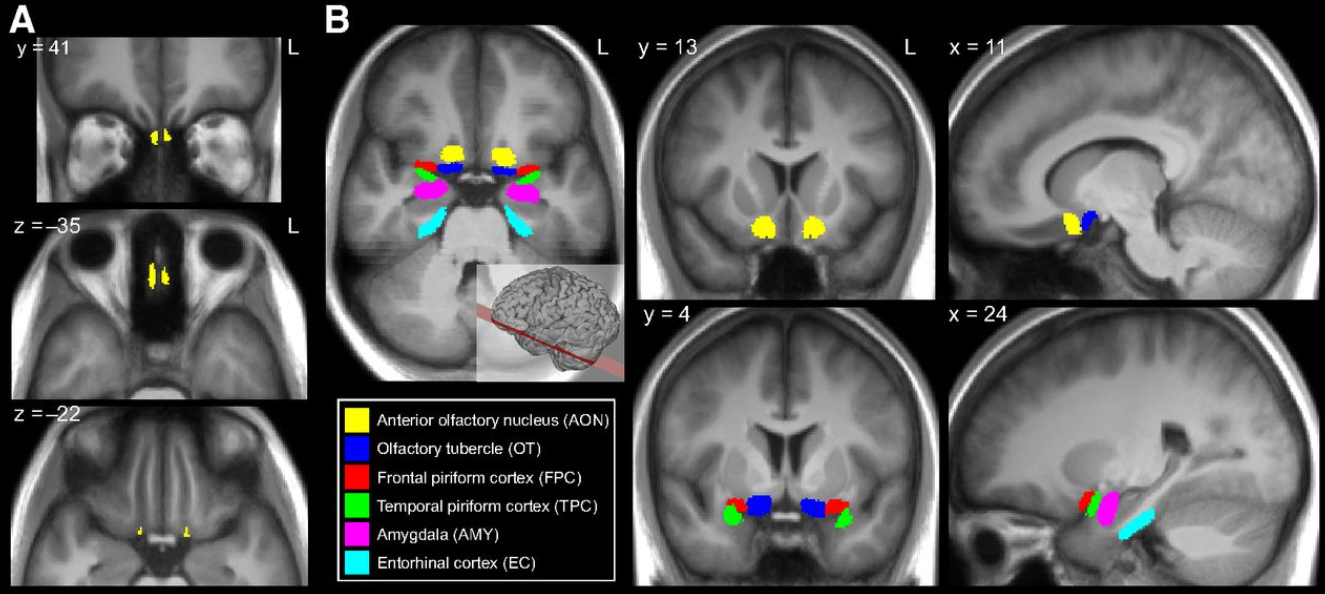

Обонятельная луковица, собирает в себя сигналы от разных рецепторов и напрямую передаёт их в первичную обонятельную кору, в обход таламуса, что уникально для сенсорных систем.

Здесь формируется основное распознавание запаха как отдельного «образца/шаблона»: «запах розы», «горелый запах», «тухлятина» и т.п. Это первая стадия, где активность разных наборов возбужденных полей нейронов превращается в осознанное восприятие запаха.

Лимбическая система (миндалевидное тело) – эмоциональная окраска запахов

Обонятельные сигналы напрямую идут в миндалевидное тело — центр тревоги, страха и других эмоциональных реакций. Это добавляет запахам мощную эмоциональную компоненту, чего нет у других чувств.

Гиппокамп – связь обоняния с памятью

Гиппокамп участвует в долговременном запоминании и ассоциациях. Обонятельные сигналы туда идут напрямую, формируя сильную связь между запахом и воспоминанием.

Орбитофронтальная кора – сознательное распознавание и оценка запахов

После обработки в обонятельной коре сигналы передаются в орбитофронтальную кору головного

Осознанное восприятие запаха - «это кофе», «это лимон», «это море».

Оценка запаха – приятен он или неприятен.

Выбор реакции на запах - понюхать или отойти в сторону от источника.

Обонятельная кора |

Первичное восприятие запаха |

Миндалевидное тело |

Эмоциональная реакция (тревога, страх, удовольствие) |

Гиппокамп |

Ассоциации и долговременная память |

Орбитофронтальная кора |

Осознанное узнавание, принятие решения |

Поясная кора |

Мотивационные и поведенческие реакции |